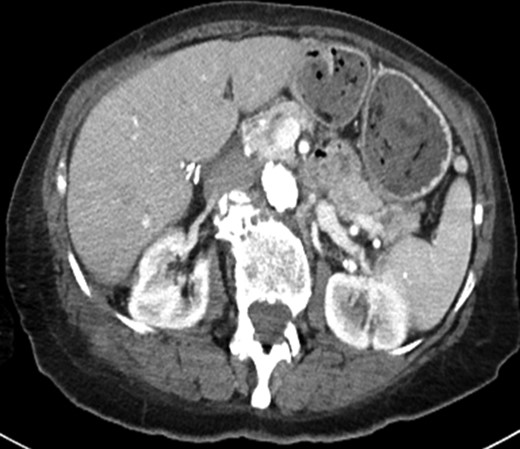

Final pathology demonstrated CD-68 positive histiocytic accumulation with bile and gallstones (Fig. 2b). The patient completed 6 weeks of postoperative antibiotics to treat culture-positive E. coli. Gallstones (Fig. 4) and fluid drained for several weeks postoperatively and then resolved. Three months after operation, a CT scan demonstrated resolution of all abnormalities (Fig. 5).

Axial CT image obtained 3 months after the patient's operation showing resolution of the solid and cystic mass.